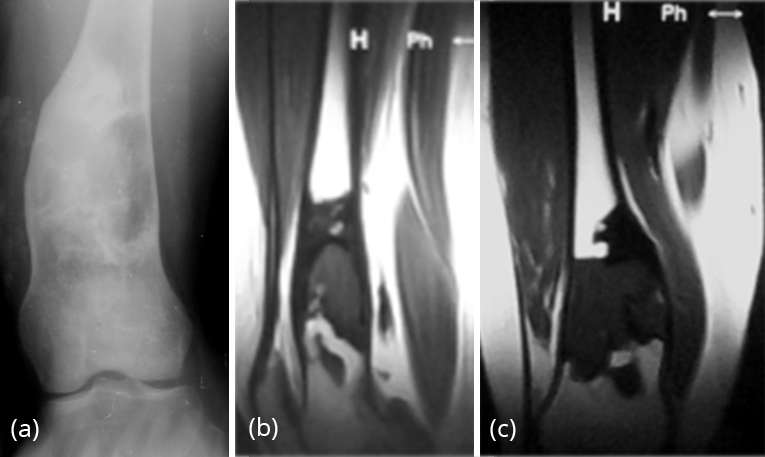

MRI – (Figure 25a,b,c)

MRI is not particularly useful in differentiating fibrous dysplasia from other entities as there is marked variability in the appearance of the bone lesions, and they can often resemble tumour or more aggressive lesions.

On T1-weighted images, the signal intensity is usually low to intermediate, depending on the ratio of fibrous tissue to mineralized matrix. Lesions with high fibrous tissue content tend to have intermediate signal intensities, whereas lesions with highly mineralized stroma tend to show lower signal intensities. On T2-weighted images, the MR signal intensities are more variable. Some lesions with a highly mineralized matrix show correspondingly low signal intensities, whereas lesions with high fibrous tissue content and cystic spaces return high signal intensities (Figure 26a,b).

Heterogeneous enhancement after administration of gadolinium is noted.

Figure 25: FD – (a) plain film, (b, c) MRI – Lower end of femur showing low intensity signal.